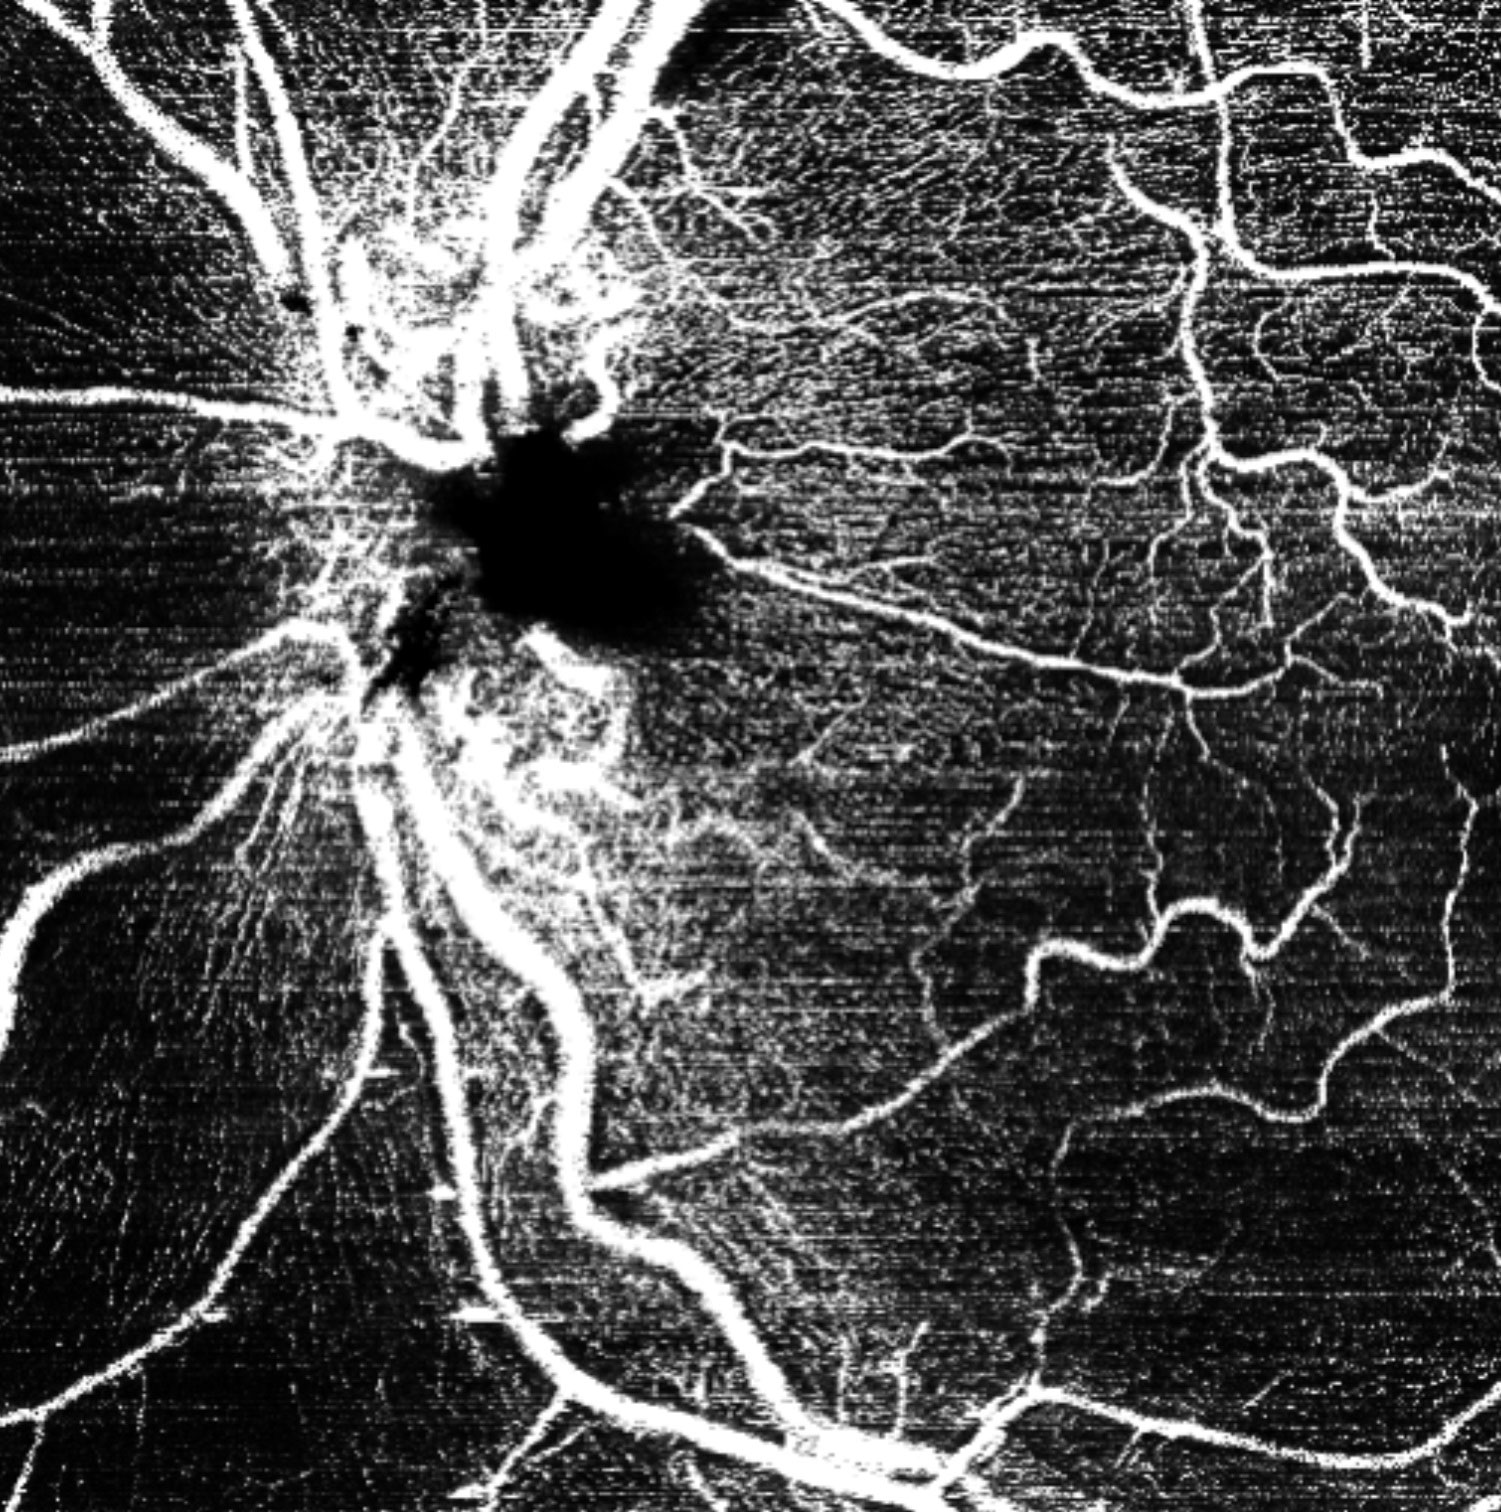

Offering the ideal speed-quality ratio for OCTA, 125 kHz allows you to increase your throughput without any clinically relevant loss in image quality in comparison to the current 85 kHz scan speed. The fast acquisition of images allows for visualization of flow, even in miniscule vessels, while minimizing artefacts, resulting in sharp and detailed images of the capillary network. Additionally, you can decrease chair time when you speed up acquisition with the Glaucoma Module Premium Edition in your glaucoma workflow, if applicable.

125 kHz – A fast scan speed for improved workflow and high OCTA image quality.